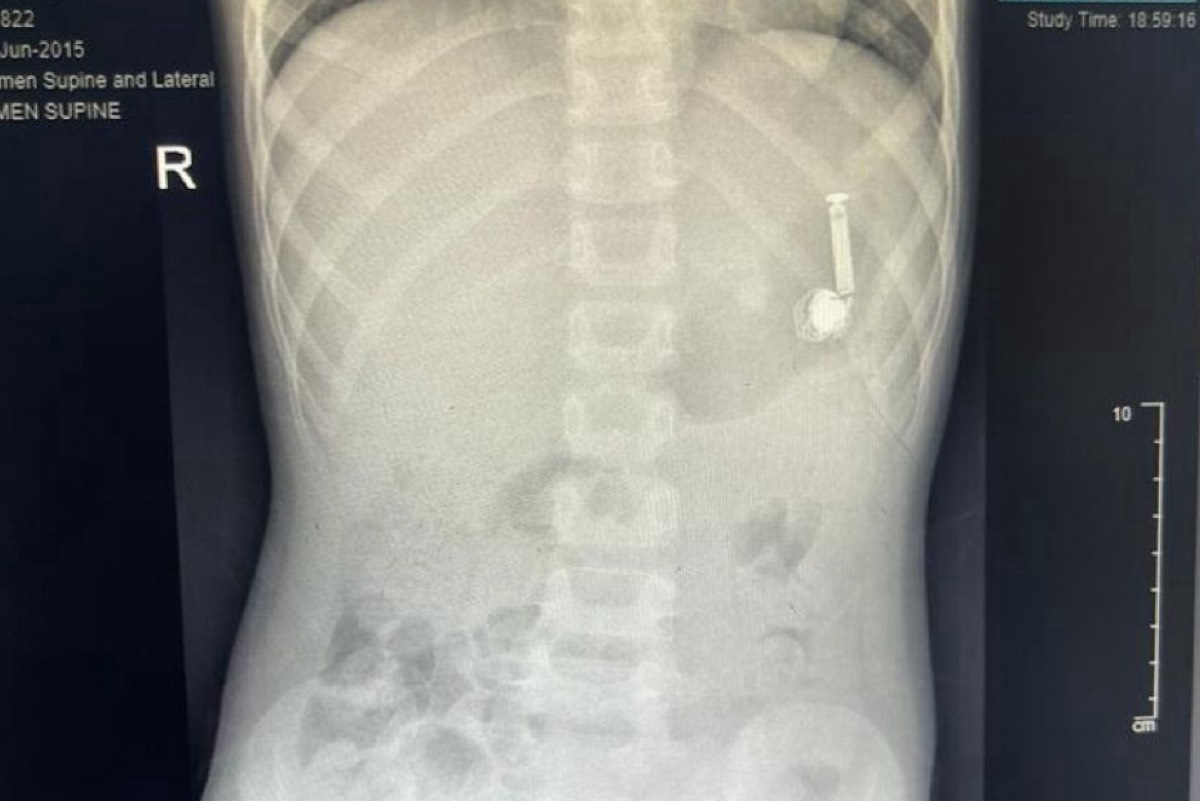

تمكَّن فريقٌ طبيٌّ بمستشفى الولادة والأطفال عضو تجمع مكَّة المكرَّمة الصحي من إخراج سمَّاعة جوَّال من داخل بطن طفل، يبلغ من العمر عشر سنوات.

الحالة وصلت لقسم الطوارئ بالمستشفى، وأخبر الأهلُ الطاقمَ الطبيَّ أنَّ ابنهم ابتلع السمَّاعة، وعلى الفور تمَّ مناظرة الحالة وعمل الفحوصات الطبيَّة اللازمة، وتمَّ تشكيل فريق طبي من قسم المناظير وقسم التخدير للتَّعامل مع الحالة، وتجهيز الطفل لعمل المنظار دون تدخل جراحي.

وتكلَّلت العمليَّة بالنجاح في وقت قياسي، تم على إثرها إزالة السمَّاعة والتأكُّد من صحَّة الطفل، وقد غادر المستشفى وهو يتمتَّع بصحَّة جيدة.